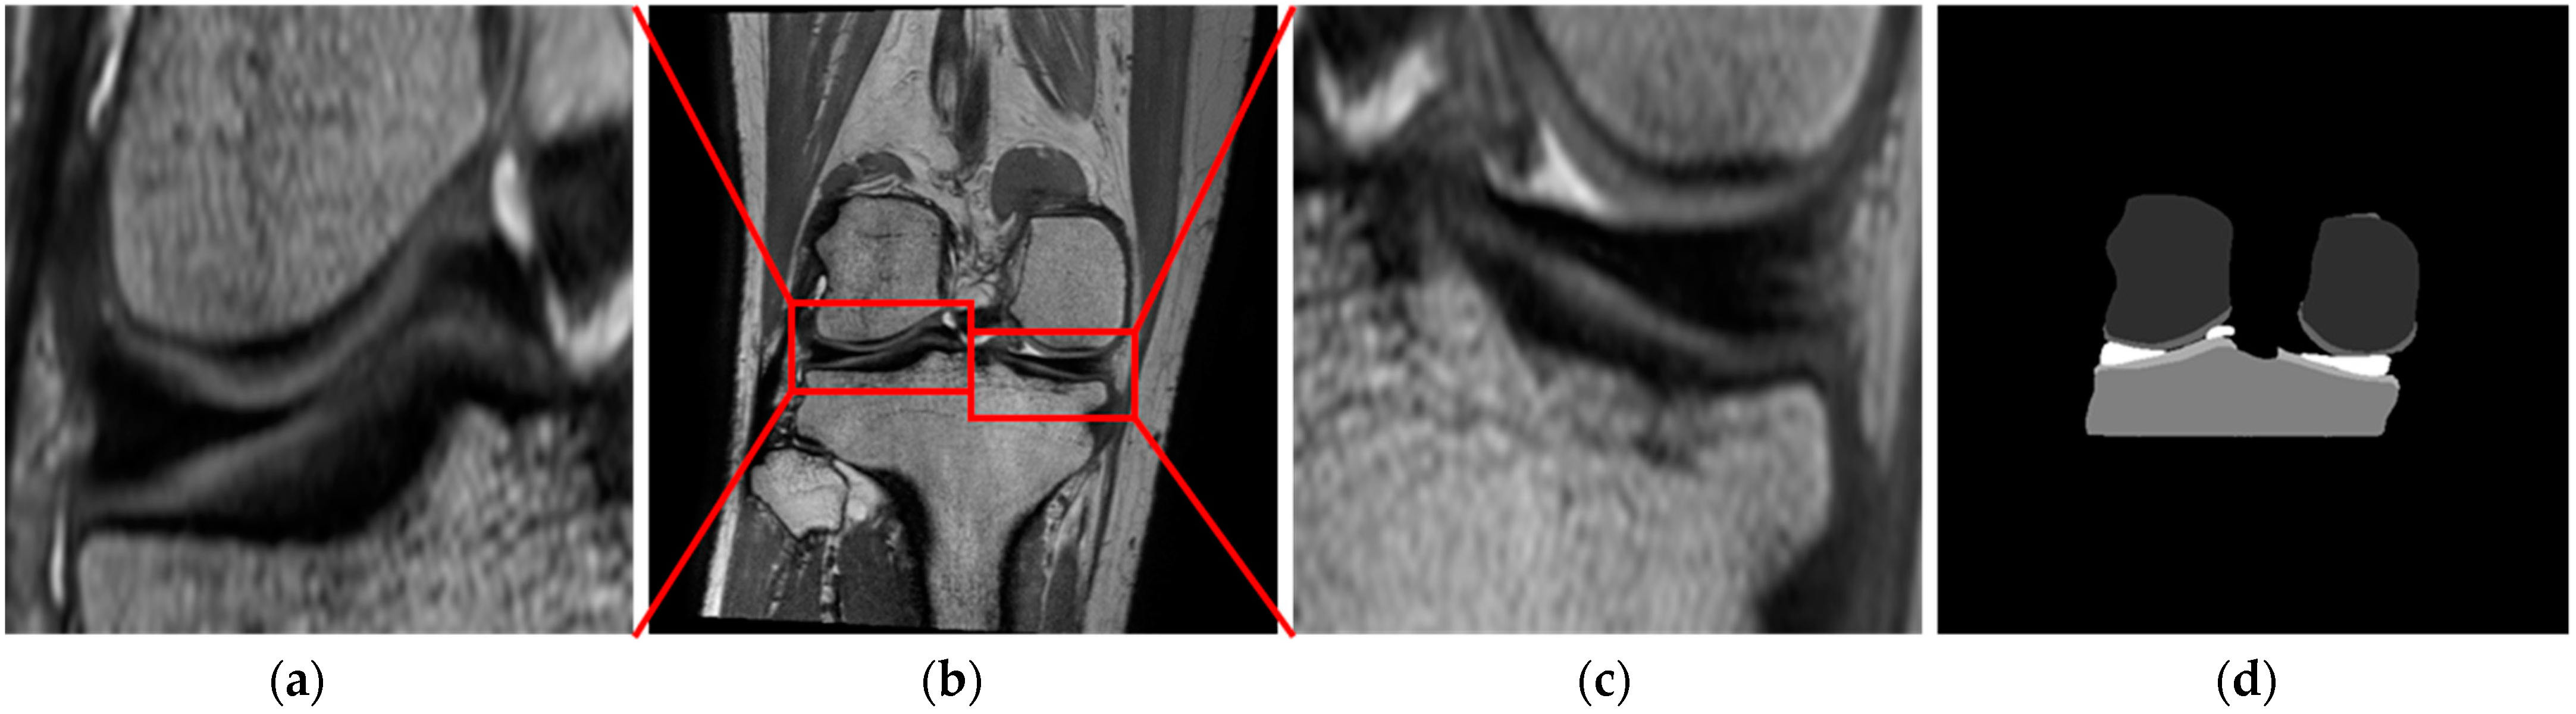

The menisci is a thin, semi lunar-like tissue pad consisting of the medial meniscus located on the inside of the knee and the lateral meniscus located on the outside of the knee, distributing the load while also reducing friction in the knee [1,2]. Automatic meniscus segmentation from knee MR images is an essential step when analyzing certain aspects of the shape of the meniscus such as the length, width, height, cross-sectional area, and surface area, as required for meniscus allograft transplantation using a 3D reconstruction model of the patient’s unruptured meniscus generated through automatic segmentation of the meniscus. In meniscus allograft transplantation, the most appropriate 3D reconstruction model for the patient can be generated by mirroring the opposite side of the knee of degeneration. However, as shown in Figure 1, automatic meniscus segmentation is challenging due to its thin shape, similar intensity to nearby structures such as the cruciate and collateral ligaments in knee MR images, the considerable shape and size variations of the anterior horn and posterior horn of the meniscus between patients, and due to inhomogeneous intensity levels within the meniscus.

Figure 1. Characteristics of the meniscus in knee MR images: (a) Structures of the lateral and medial meniscus in the axial view; (b) Similar intensity of the medial meniscus and collateral ligaments in the coronal view; (c) Shape variances of anterior and posterior horns of the meniscus among patients; (d) Inhomogeneous intensity of lateral and medial meniscus (yellow arrow) in knee MR images.